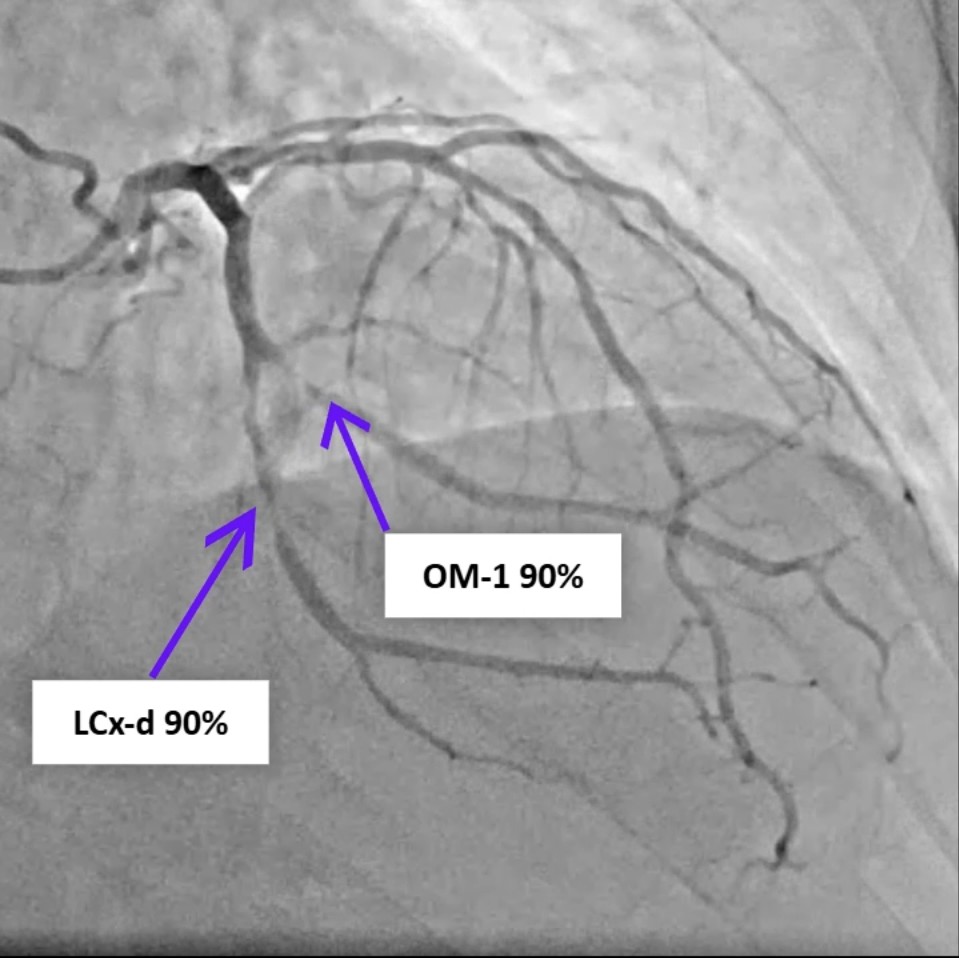

A 77-year-old man with hypertension, diabetes, and prior coronary artery disease presented with progressively typical angina for several days and was diagnosed with non-ST-elevation myocardial infarction. He underwent successful percutaneous coronary intervention with drug-eluting stents to the distal left circumflex and obtuse marginal (OM-1) branch, achieving TIMI-3 flow. Eight hours later, he developed sudden dizziness, diaphoresis, hypotension, and jugular venous distention.

Relevant Catheterization Findings

Review of the primary PCI angiography revealed no contrast extravasation; however, the Sion wire had advanced deeply into a small distal branch of the LCx artery, in hindsight possibly causing a distal micro-perforation. Repeat angiography demonstrated patent stents in both the left circumflex and obtuse marginal branches without in-stent thrombosis. No persistent or visible extravasation was noted, suggesting spontaneous hemostasis of the suspected micro-perforation.